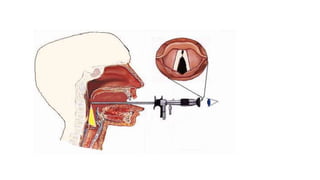

LARYNGOSCOPY-

Laryngoscopy may be performed at any time,

although it is recommended when hoarseness does

not resolve within three months of onset or if a

serious underlying cause is suspected.

Visualizing the larynx and vocal folds is important in

a patient presenting with hoarseness, especially if

symptoms persist.

Indirect laryngoscopy using flexible fibrescope.

LARYNGOSCOPY- Laryngoscopy may beperformed at any time, although it is recommended when hoarseness does not resolve within three months of onset or if a serious underlying cause is suspected. Visualizing the larynx and vocal folds is important in a patient presenting with hoarseness, especially if symptoms persist.

Indirect laryngoscopy usingflexible fibrescope.